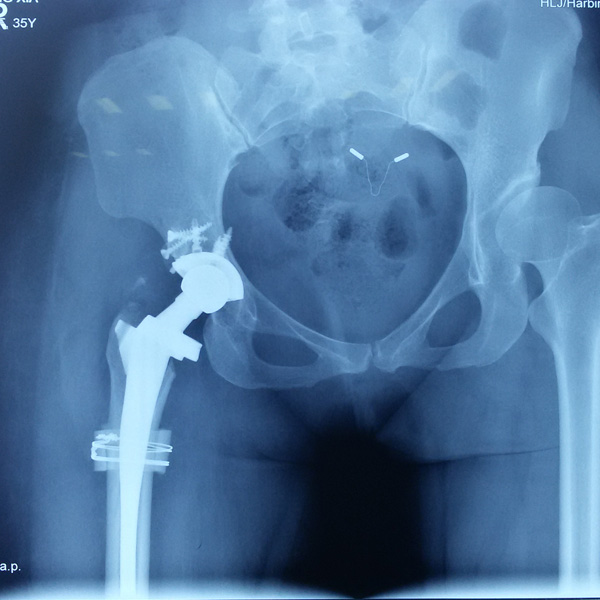

手術(shù)后手術(shù)前

髖關(guān)節(jié)翻修

患者蘇某,女性,11年前因“左髖關(guān)節(jié)屈曲攣縮畸形”行左側(cè)人工全髖關(guān)節(jié)置換,近來感覺左髖關(guān)節(jié)疼痛,不敢行走,經(jīng)“攜生醫(yī)療平臺”就診于哈......